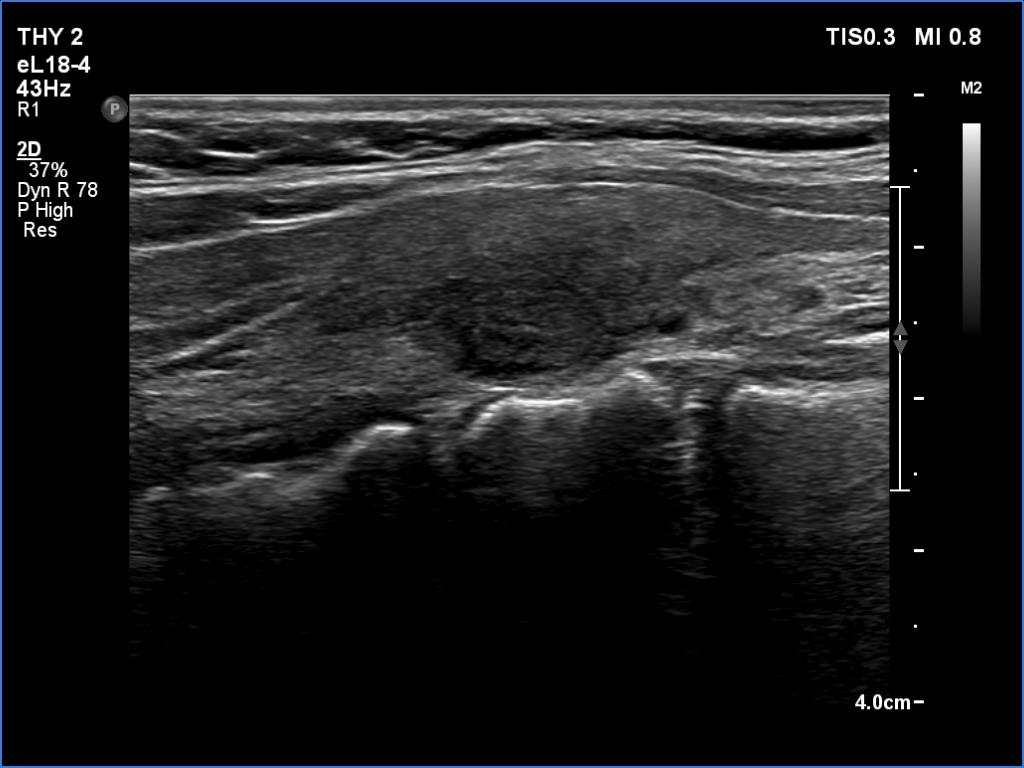

Lymphocytic thyroiditis - case 1441

Right lobe

Focal form of lymphocytic thyroiditis is presented. The thyroid has numerous discrete, hypoechoic lesions which correspond to more active foci of thyroiditis. The interpretation of the relatively large ventral hypoechoic area in the left lobe (right upper image can cause problem), however, longitudinal scan decides the issue: this field cannot be a pathological nodule.